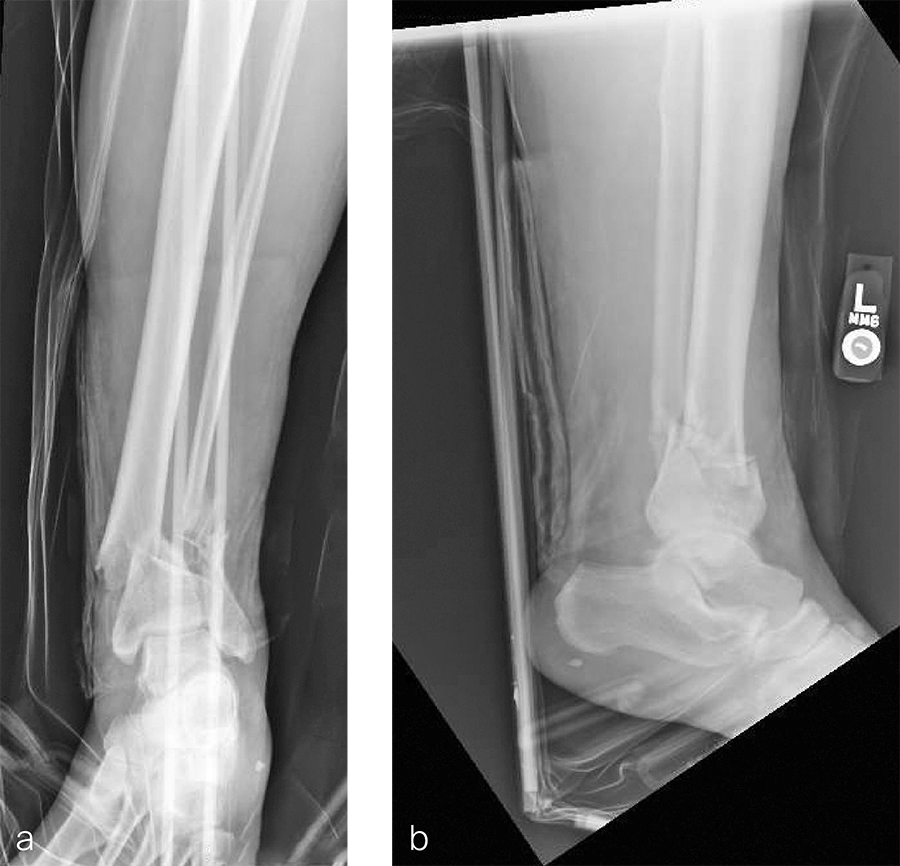

A 59-year-old man working for the city of Tulsa suffered an open distal tibia plafond fracture on the left leg when he fell into a sewer hole with raw sewage (Fig 1). The wound was grossly contaminated, and he was taken immediately to the operating room (OR) for incision and drainage and application of a spanning external fixator. Bone loss was noted anterior and medial (about 2.5 or 3 cm) but only about 2025% of the bone circumference.